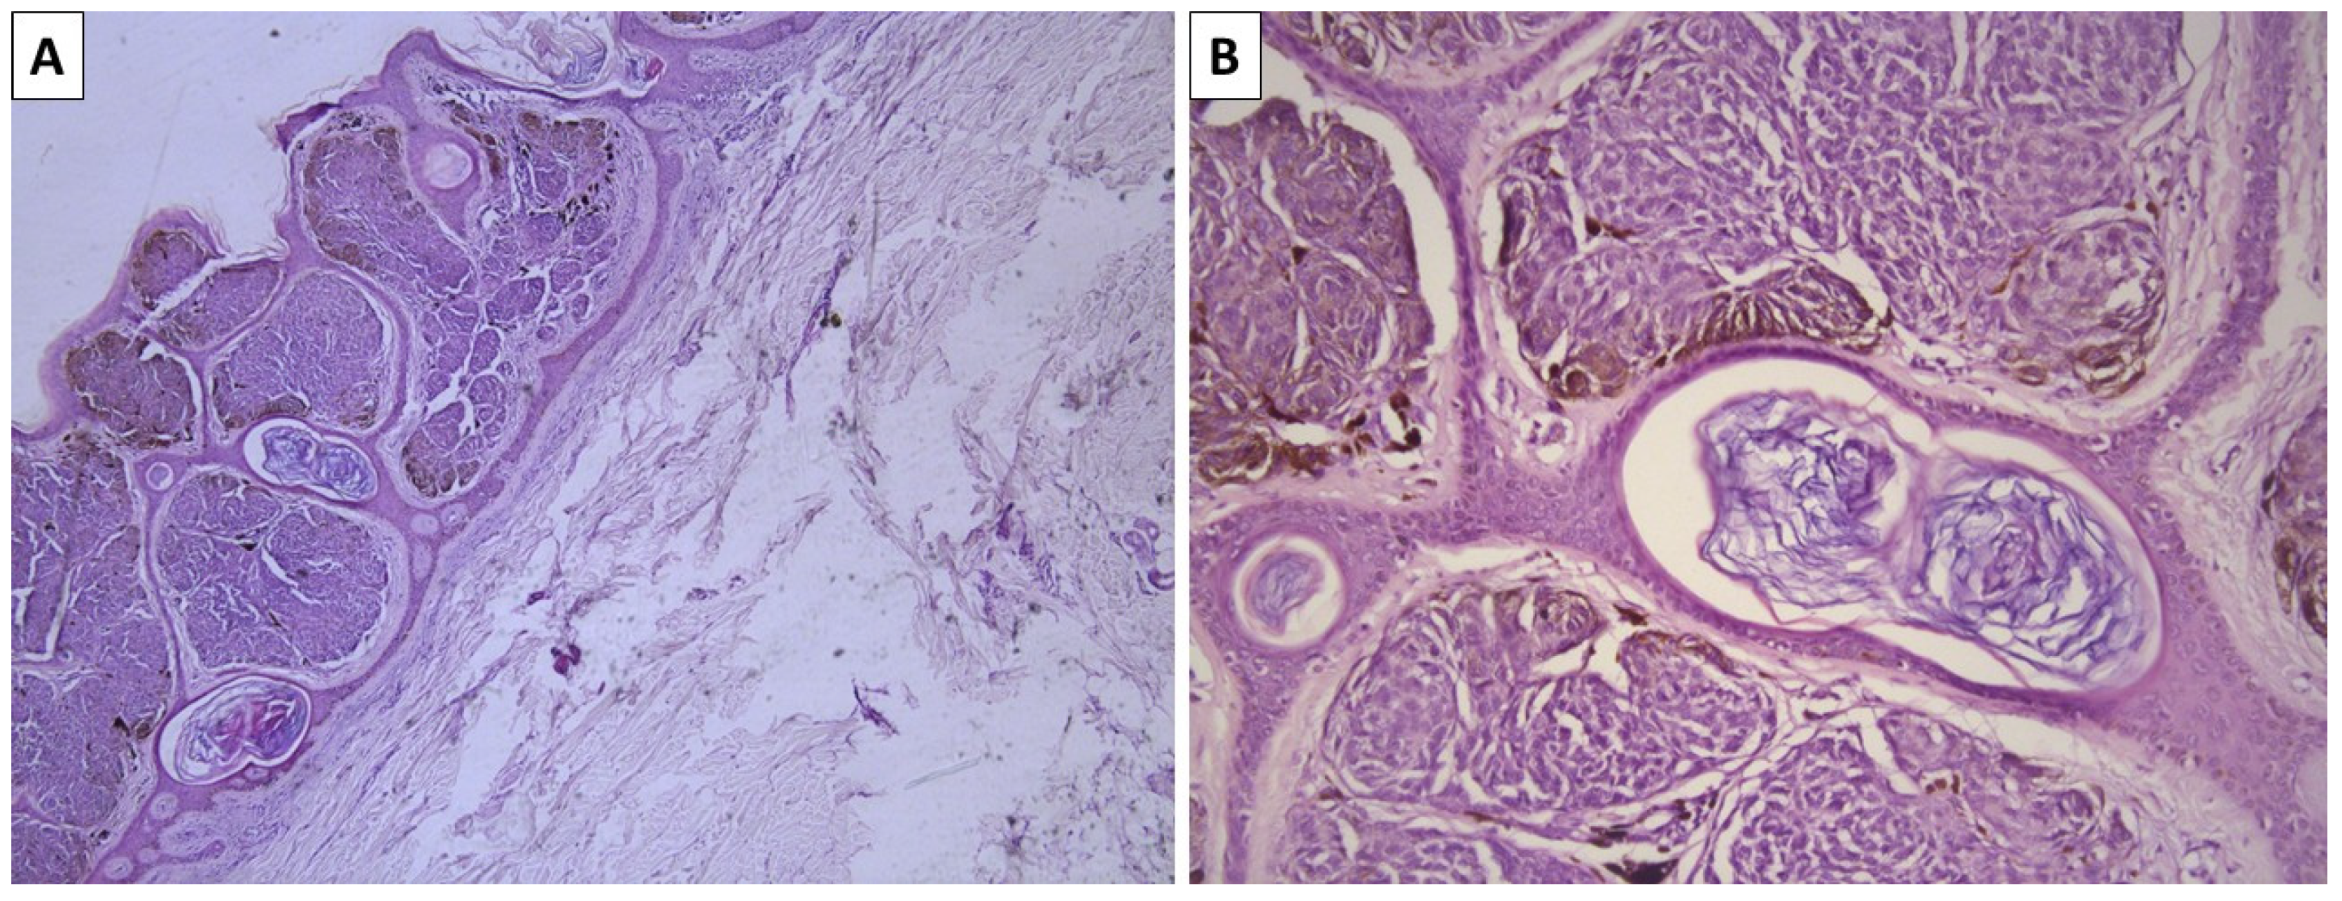

2.2. Case 3—Conventional Cellular Blue Nevus